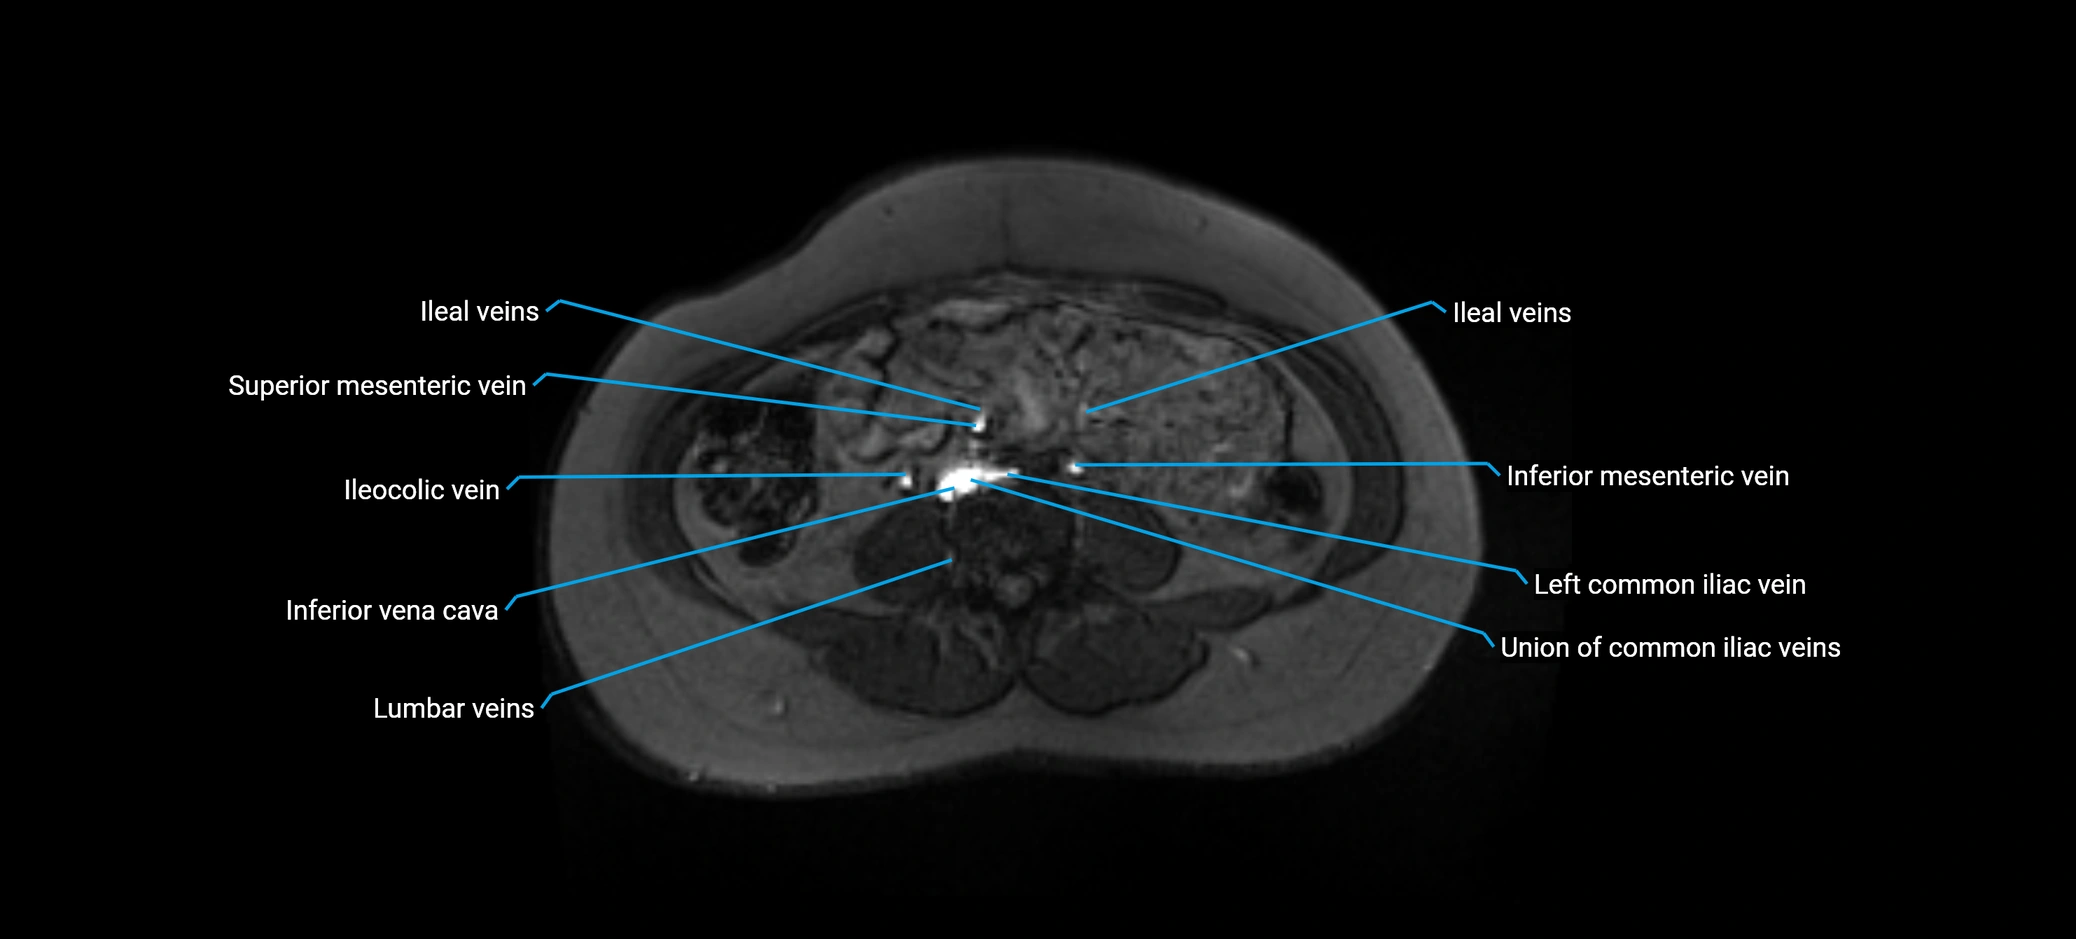

MRI image

image